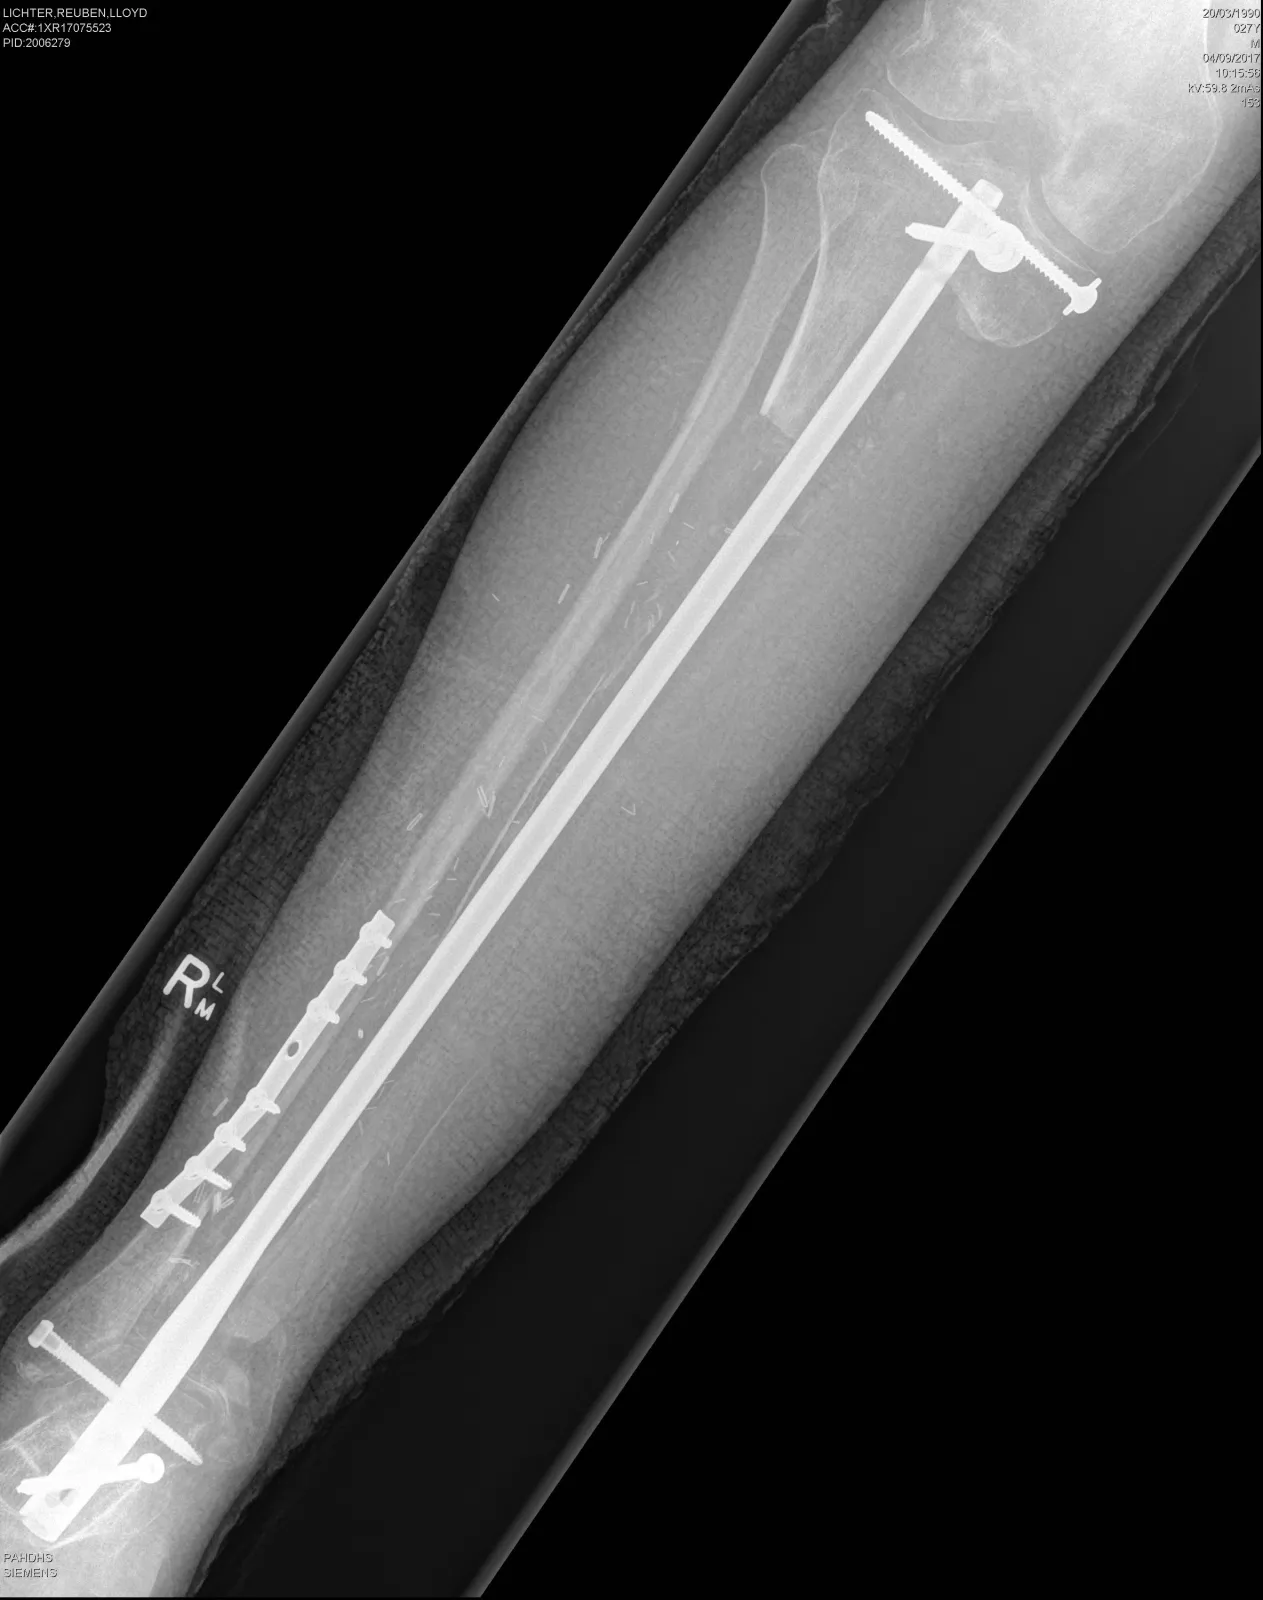

3 Zdjęcie rentgenowskie nogi pacjenta jeszcze przed wszczepieniem nowej kości...

PAP/EPA / PRINCESS ALEXANDRA HOSPITAL HANDOUT